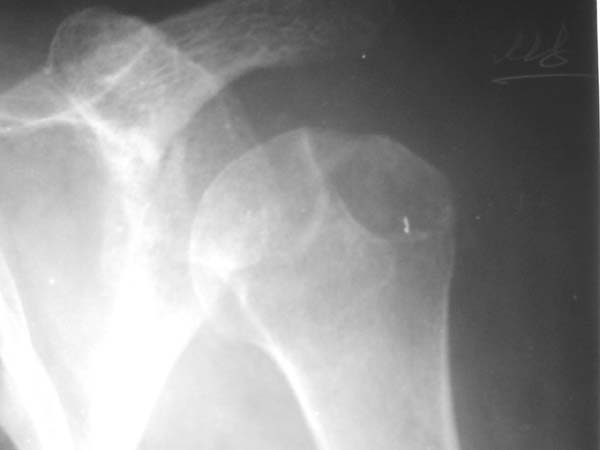

r1r2r3

Уважаемые коллеги!Женщина, 60 лет. 3 недели назад упала с упором на отведенную левую руку. Почувствовала боль в левом плечевом суставе. За помощью не обращалась. 2 недели "мази и припарки". Затем - рентгенограмма (r1 и r2), жалобы на боли,ограничение движений...

Активное отведение 80 гр., при пальпации - головка плечевой кости безболезненно вправляется и тут же самостоятельно вывихивается. Наложена косыночная иммобилизация, рентгенография (r3) и МРТ.В нашем диагностическом центре МРТ исследование плечевого сустава выполнено впервые, опыта у нас маловато :(.Вопросы: уточнение диагноза? какие исследования провести? тактика лечения?

"Прицельная" съемка малопонятного очага.

1. На рентгене - нижний подвывих плеча и очаг остеолиза суставного бугорка с четкими контурами (вдавленный перелом на фоне остеопороза ? доброкачественная опухоль? аваскулярный некроз ? (хотя ни разу не слышал об аваскулярном некрозе плеча..)

Судя по снимкам, речь идTт о типичном случае Hill-Sachs Lesion. По этому поводу я позволю себе некоторый экскурс:

97 % всех вывихов плеча происходит по механизму комбинации отведения, разгибания и наружной ротации (А. Гринспан). В момент вывиха головка плеча ударяет о нижний край гленоида, что ведет к вдавленному или компрессионному перелому одной или обеих структур. Чаще всего, однако, повреждение возникает в задней латеральной области головки плечевой кости на переходе от головки к шейке. Этот диагноз можно выставить на основании рентгеновского снимка в переднезадней проекции с внутренней ротацией плеча. Несколько реже видно повреждение гленоида о передненижний перелом края. То, что мы называем Bankart Lesion. Это повреждение видно на ре. снимке в п.з. проекции при нейтральной позиции плеча. Разумеется хрящевые и мягкотканные повреждения (в смысле Банкарт) мы увидим лучше всего на ЯМР.